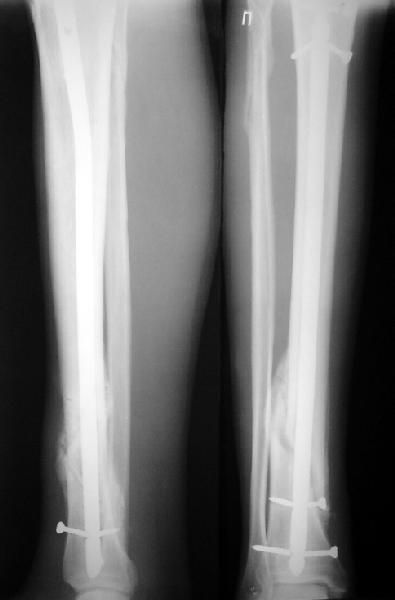

На мой взгляд, на снимках, приведённых Вами - неправильно сростающийся перелом дистальной трети большеберцовой кости, состояние после остеосинтеза интрамедуллярным гвоздём.

Как Вы пишите снимок под номером 1 - менсяц после операции, под номером 2- два месяца после операции.

I think that the X-Rays show S/P IMN of Spiral # of the Distal Tibia consoles in misalignment.

You wrote that a picture number 1 - f month after the surgery, and number 2-two months after the surgery.